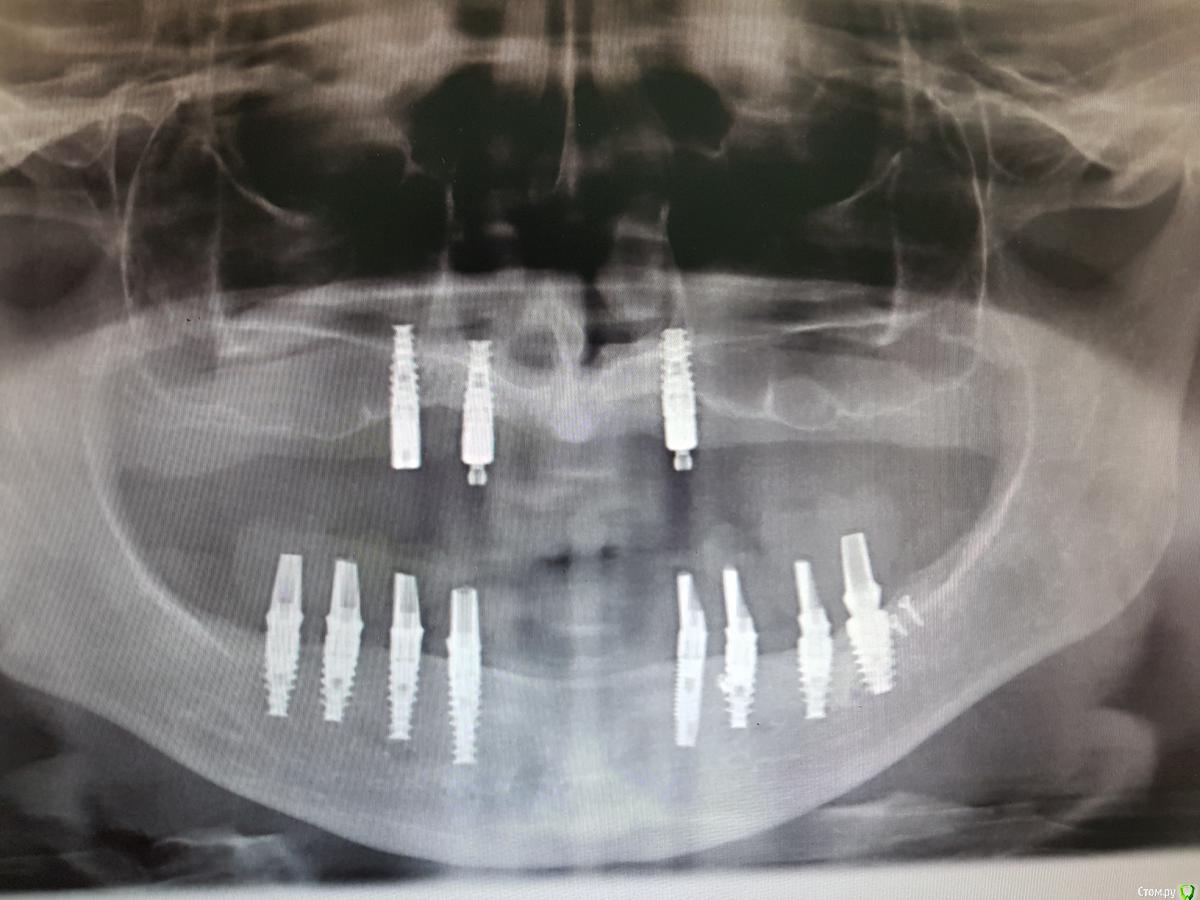

Rash163 Опубликовано 9 ноября, 2013 Поделиться Опубликовано 9 ноября, 2013 Работе после сдачи 1,5 года. Фото до протезированию нет, потерялись с телефоном( mis locator. Пока полет нормальный 2 Ссылка на комментарий

anvladd Опубликовано 10 ноября, 2013 Поделиться Опубликовано 10 ноября, 2013 Работе после сдачи 1,5 года. Фото до протезированию нет, потерялись с телефоном( mis locator. Пока полет нормальныйпочему только 2 импланта? Ссылка на комментарий

anvladd Опубликовано 10 ноября, 2013 Поделиться Опубликовано 10 ноября, 2013 3 же вроде минимум 4 в идеале? Ссылка на комментарий

mapmax Опубликовано 24 октября, 2016 Поделиться Опубликовано 24 октября, 2016 Сейчас нахожусь на этапе выбора системы крепления верхнего протеза. Имплантолог "постарался",что из 6 болтов, "выжило" только три. Делался синус(не вижу там его). Пациентка крайне не желелает более каких либо хирургических вмешательств. Ссылка на комментарий

chervoncevdaniil Опубликовано 25 октября, 2016 Поделиться Опубликовано 25 октября, 2016 По моему для ВЧ минимальное количество имплантов-это 4, меньшее просто убьет импланты,не советую с 3 рисковать Ссылка на комментарий

red_butler Опубликовано 25 октября, 2016 Поделиться Опубликовано 25 октября, 2016 фактически на верху только два винта 1 Ссылка на комментарий